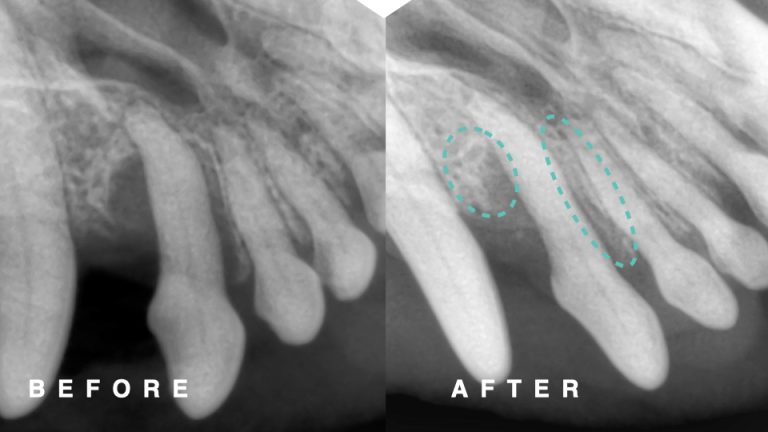

下の写真は犬歯が折れてしまった猫ちゃんです。

レントゲン検査では根尖病変を疑う所見はありませんでしたが、

破折から時間が経ってしまていたため、神経を抜く抜髄治療を行いました。